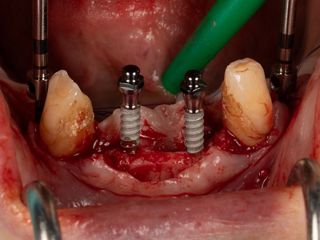

3a. Elevation of the full-thickness flap by crestal incision centred on the keratinised and sulcular tissues in 33 and 43.

The canines are preserved to provide an indication of the drilling axis.

3a

3b

3b. Drilling adjacent to the remaining teeth 33 and 43 using the initial 1.5 mm drill. Depth and axis checked using the anterior indicators and residual canines.

Given the average bone density (D2 to D3), only the initial drill was used to the working length of 12 mm.